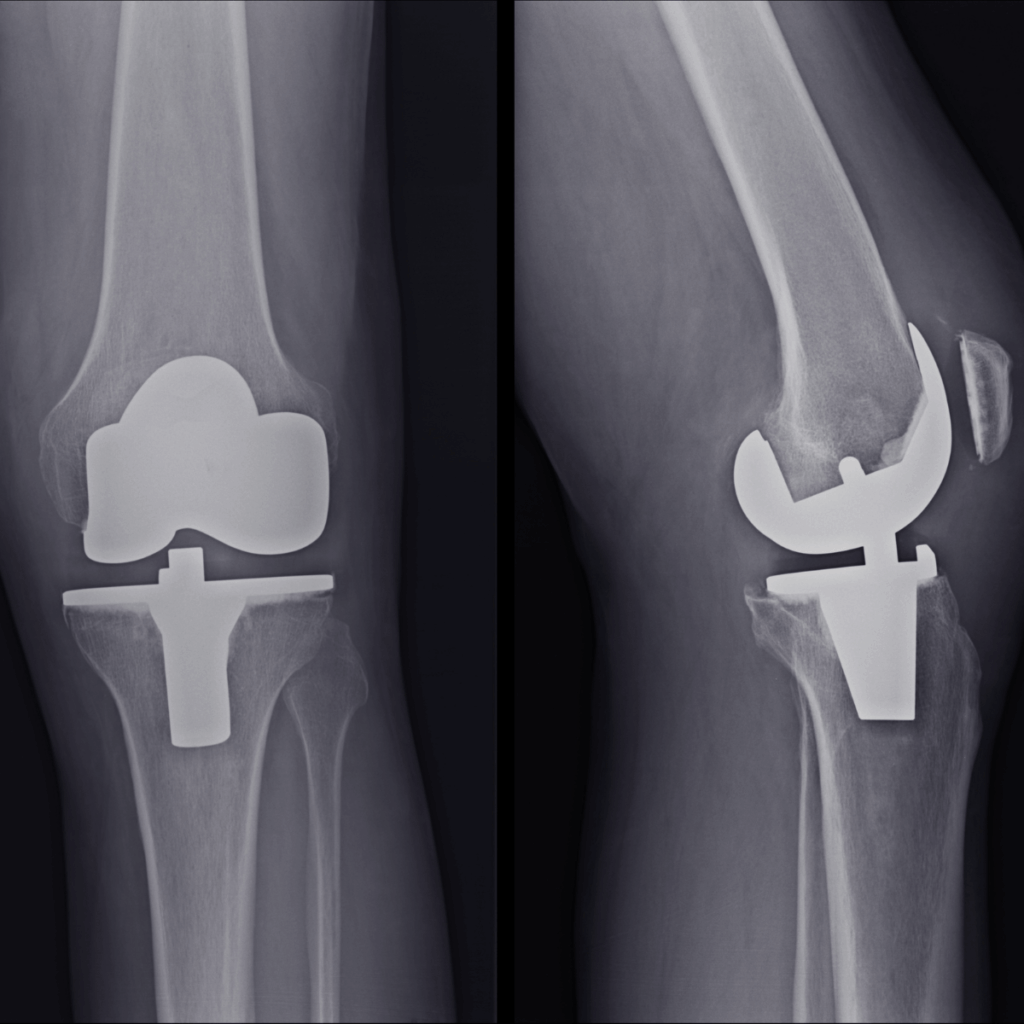

Surgical Procedure

Damaged cartilage and bone are removed

Metal and plastic implants are fitted to restore knee alignment

Advanced options like robotic-assisted surgery ensure precise implant placement